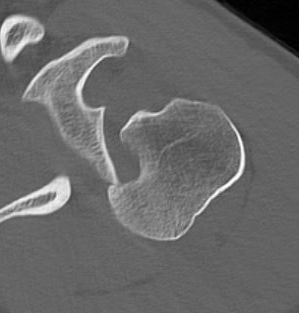

CT scan

Confirms dislocation

Reverse Hill Sachs

Humeral head defect

- caused by impaction of anterior humeral head on posterior glenoid

- intra-articular

- measured as a percentage of the articular surface